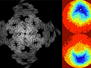

Viruses have a reputation for causing us harm but a special group of viruses which target tumour cells – oncolytic adenoviruses – are now being developed to treat cancer. Researchers look at the potential of one such virus called Ad5/3. Mice with compromised immune systems and tumours had Ad5/3 injected into their bloodstream. Ad5/3 was able to bind to and then be released from blood cells, as captured here on a white cell using scanning electron microscopy. Travelling on these cells, Ad5/3 (red) reached, invaded and specifically killed tumour cells. What’s more, it was able to do this in the presence of neutralising antibodies, which the body creates to destroy viruses. This provides new hope for Ad5/3 as a future cancer therapy.